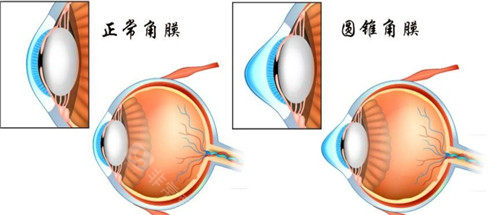

圆锥角膜是一种令人困扰的眼科疾病,而圆锥角膜交联手术为患者带来了希望。